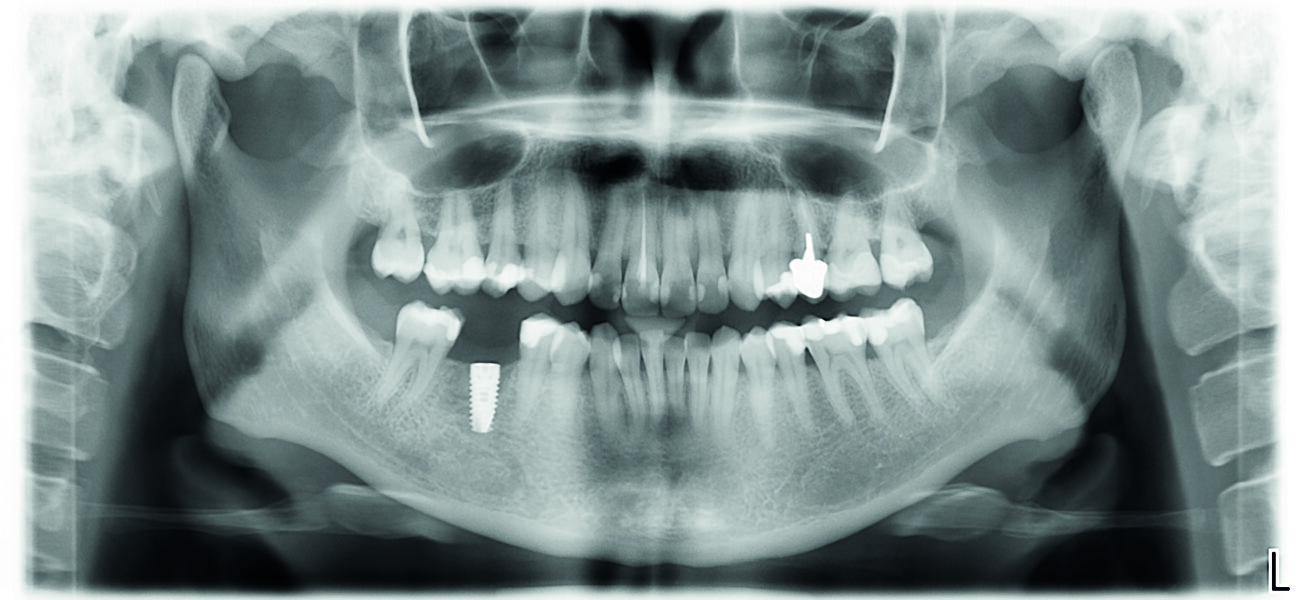

Examen clinique et radiologique L’examen clinique et radiographique met en évidence la possibilité de poser un implant (Figs. 1 et 2).

Fig. 1 : Radio panoramique, on visualise bien le secteur édenté en 46.